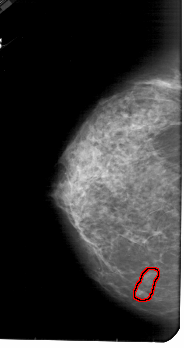

A_1842_1.LEFT_CC

LEFT_CC LINES 5206 PIXELS_PER_LINE 2746 BITS_PER_PIXEL 12 RESOLUTION 43.5 OVERLAY

FILE: A_1842_1.LEFT_CC.OVERLAY

TOTAL_ABNORMALITIES 1

ABNORMALITY 1

LESION_TYPE MASS SHAPE LOBULATED MARGINS CIRCUMSCRIBED

ASSESSMENT 4

SUBTLETY 3

PATHOLOGY BENIGN

TOTAL_OUTLINES 1

BOUNDARY